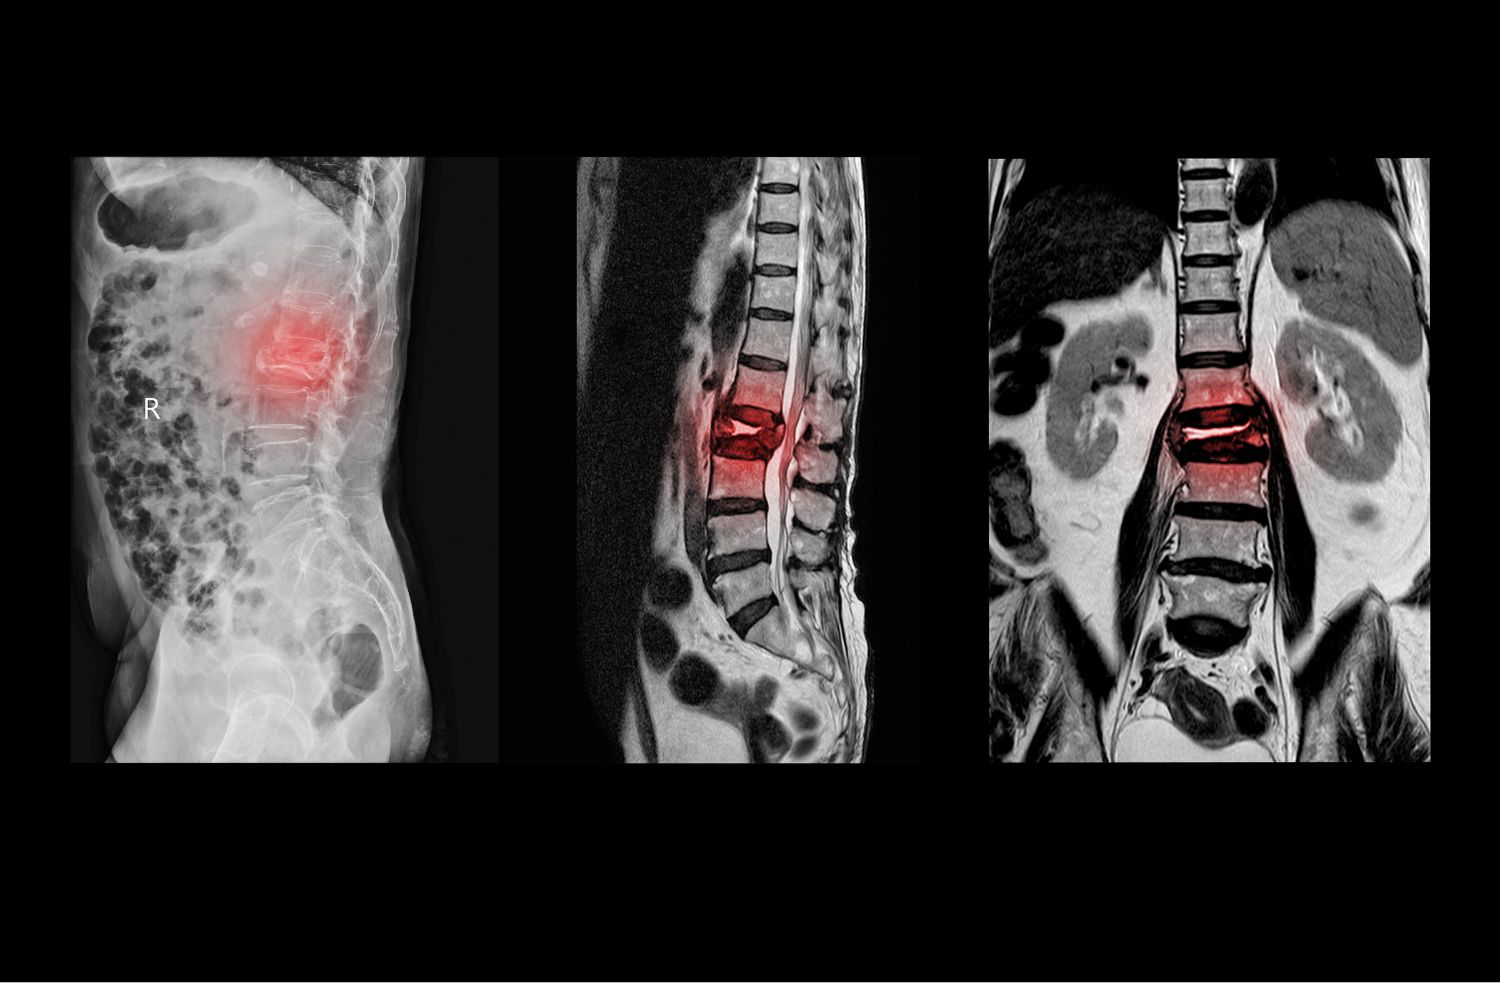

이로 인해 척수와 신경근을 직접적으로 누르고 혈류장애를 일으켜 증상이 나타나게 되는 것이지요. 이런 퇴행성 척추관 협착증은 운동량이 많은 요추 및 경추에서 많이 발생합니다.

척추관 협착증의 정확한 진단을 위해서는 영상검사가 필요합니다. 대표적인 영상검사로는 X-선, CT, MRI 등이 있습니다. 이러한 검사를 통해 척추의 구조와 크기, 뼈와 디스크의 이상 등을 확인할 수 있습니다.